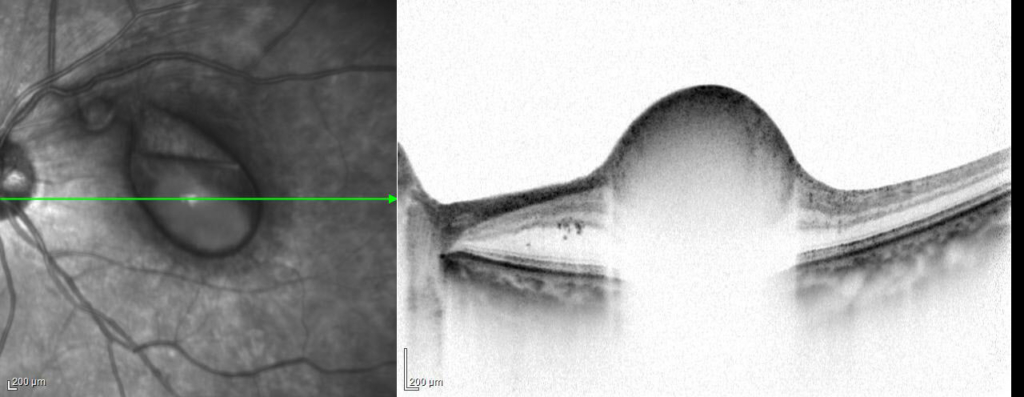

中心窩を含む鏡面形成を伴う出血がみられる。その鼻側上方に白色隆起性病変がみられる

内境界膜下 subinternal limiting membraneに出血がみられる